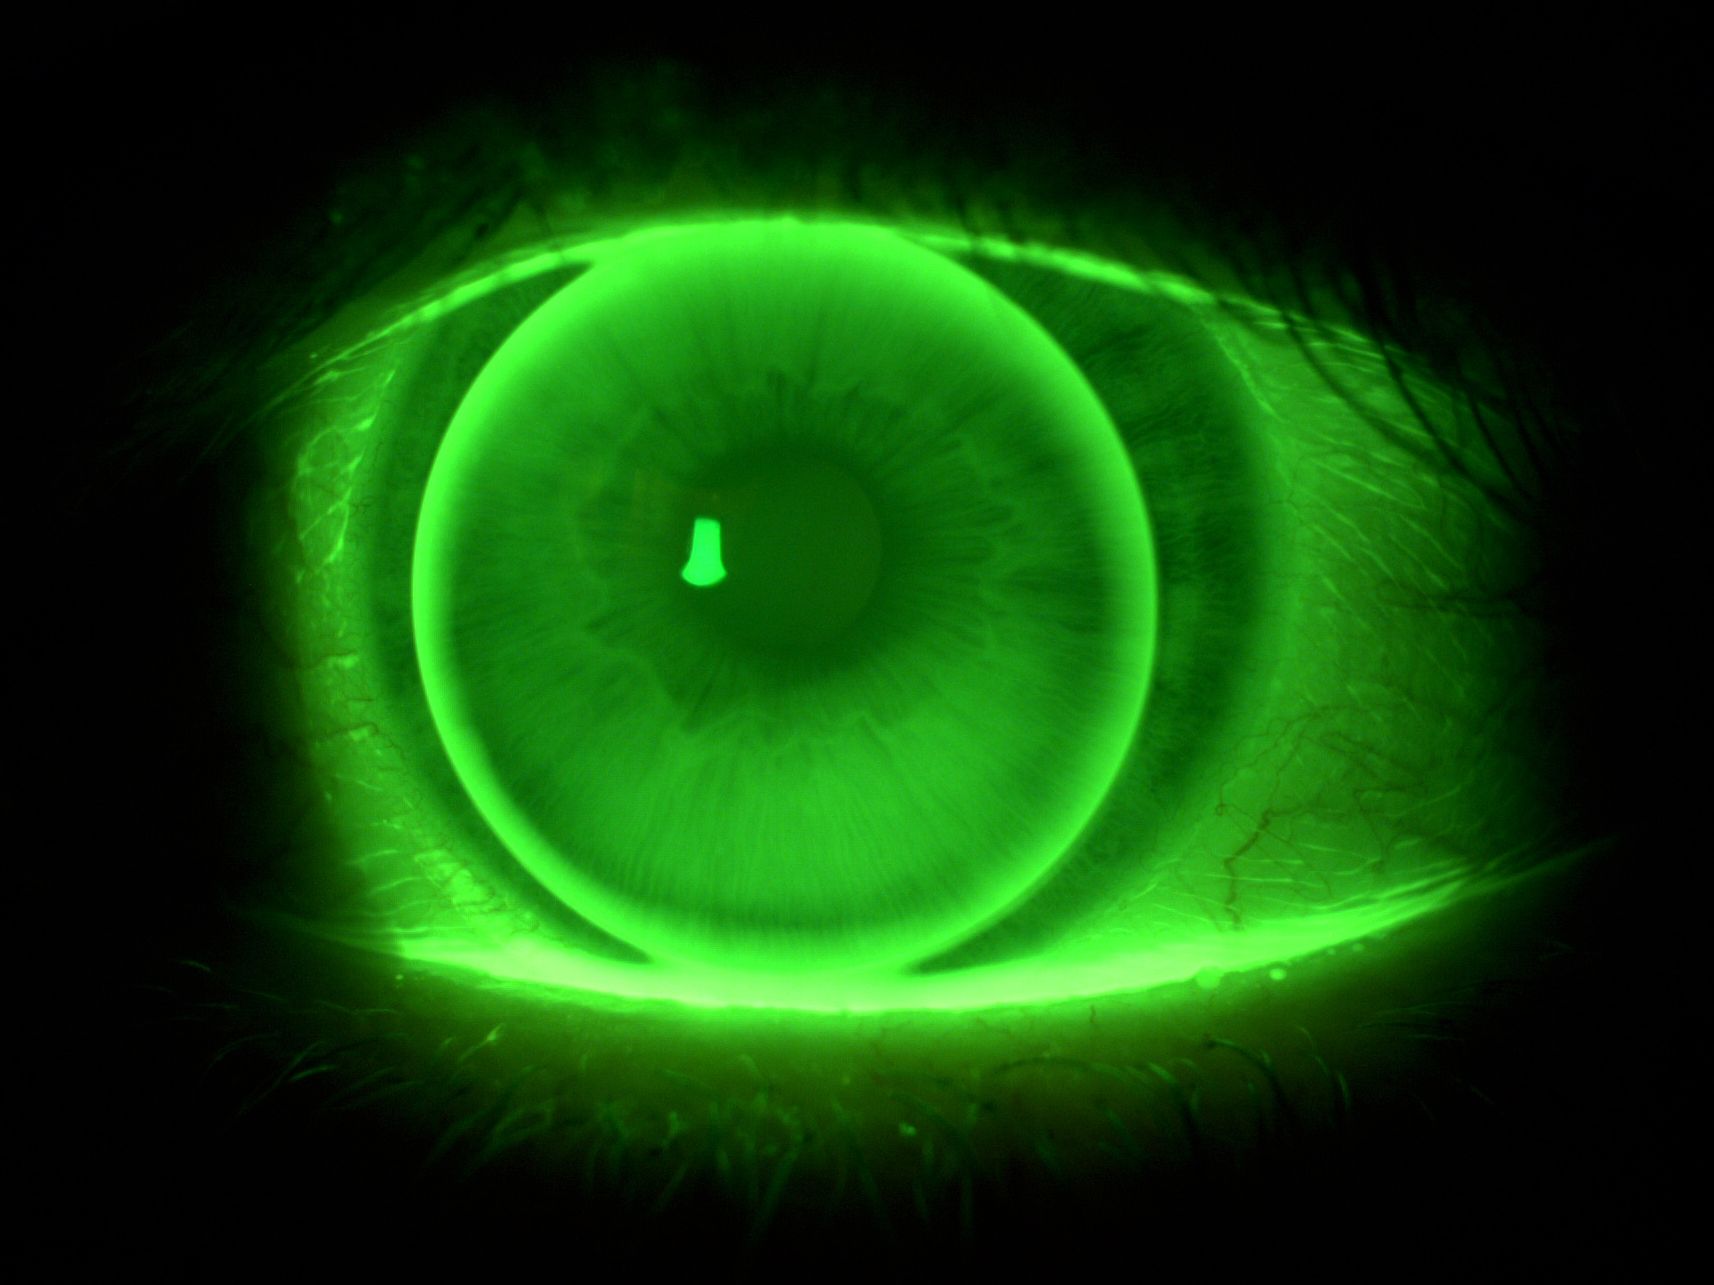

- Oprogramowanie komputerowe do indywidualnej konstrukcji soczewek kontaktowych oraz symulacji ich obrazu fluoresceinowego